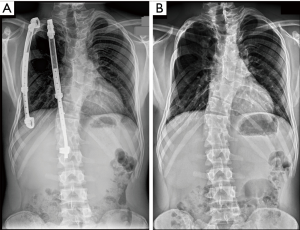

The primary indication for VEPTR is the presence of TIS in skeletally immature patients. From an anatomical point of view, in addition to absent ribs, constrictive chest wall syndrome (including fused ribs and scoliosis), hypoplastic thorax, or early onset scoliosis (EOS) of congenital or neurogenic origin without rib anomalies also qualify for VEPTR treatment. The adequate VEPTR expansion thoracoplasty strategy is based on the three-dimensional type of volume-depletion deformity (VDD) of the thorax (4) (Figure 1).

Type I is characterised by absent ribs and scoliosis, resulting in a unilateral thoracic hypoplasia. The lung prolapses into the chest with progressing loss of lung volume. In type II VDD, scoliosis is associated with fused ribs leading to a constriction and shortening of the affected hemithorax. A foreshortened thorax with bilateral longitudinal constriction of the lungs, as in Jarcho-Levin syndrome, is categorized as type IIIa, and a transverse constricted thorax, as in Jeune asphyxiating thoracic dystrophy, is described as type IIIb. For type I VDD, VEPTR expansion thoracoplasty is considered a stabilization expansion thoracoplasty. The operative goal is to increase the space available for the lung by stabilizing the flail chest wall segment and laterally expanding and lengthening the collapsed hemithorax, usually using two rib-to-rib VEPTR devices. An opening wedge thoracostomy is performed for type II VDD using a rib-to-rib VEPTR to stabilize the correction. An additional hybrid VEPTR (rib-to-lumbar spine or pelvis) is used depending on age of the patient, severity of the deformity, and the development of an adjacent compensatory thoracolumbar or lumbar curve. Staged bilateral opening wedge thoracostomies for type IIIa VDD and staged bilateral dynamic segmental expansion thoracoplasties for type IIIb VDD are recommended (Figure 2).